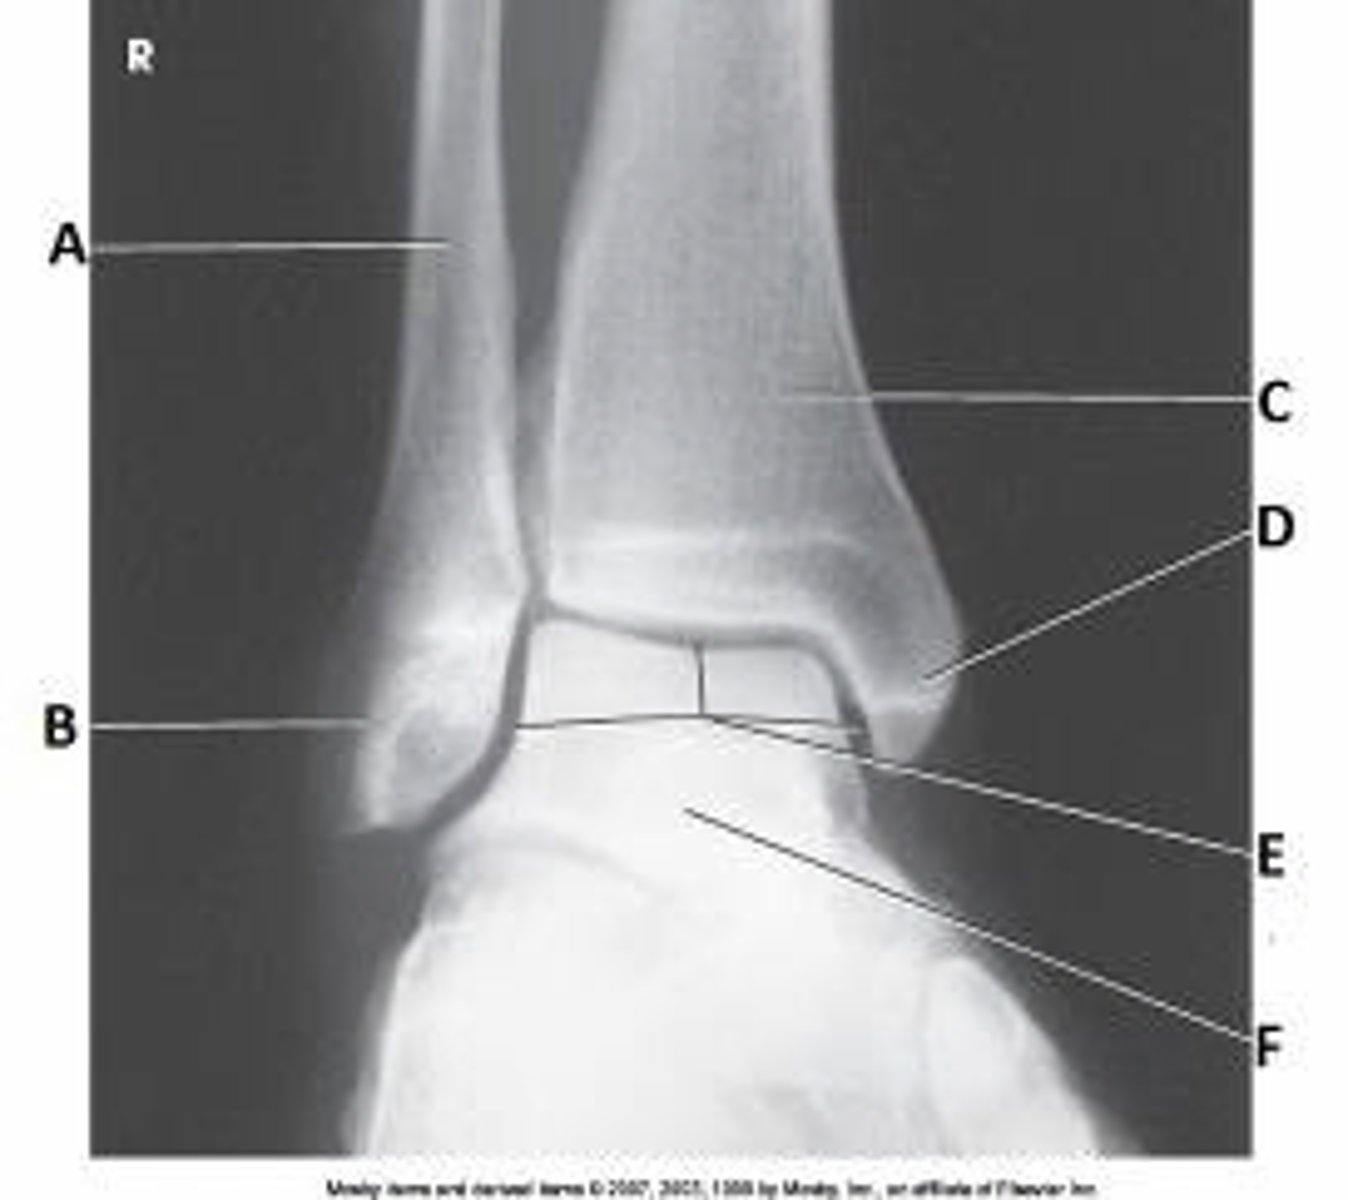

What anatomy is labeled as letter E in the image below?

Mortise joint

Tibiotalar joint

Lateral malleolus

Talus